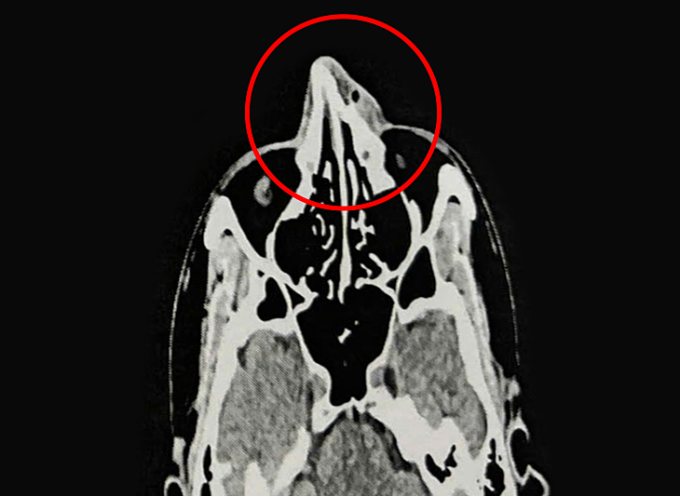

Kết quả nội soi và chụp CT 128 lát cắt ghi nhận xương mũi của anh Phi bị gãy ở vị trí tháp mũi, phù nề tụ khí mô mềm vùng mũi, lệch vách ngăn mũi, viêm mũi xuất tiết. ThS.BS.CKI Nguyễn Trung Nguyên, Trung tâm Tai Mũi Họng, Bệnh viện Đa khoa Tâm Anh TP HCM, cho biết vỡ xương mũi (gãy xương mũi) là loại gãy xương mặt phổ biến nhất do mũi ở vị trí trung tâm mặt và nhô ra trước. Chấn thương thường xảy ra do tai nạn, ngã hoặc va đập trong thể thao như anh Phi.